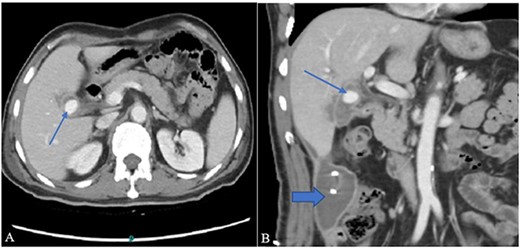

Contrast-enhanced computer tomography (CECT) abdomen showed a walled-off collection in the GB fossa measuring 44 × 19 mm with a rent identified in the first segment of the duodenum showing fistulous communication with the collection. There was also another collection, measuring 93 × 54 × 37 mm, in the right paracolic gutter with a thin streak tracing along the subhepatic margin. In addition to the fistula, a post-traumatic focal pseudoaneurysm measuring 13 × 15 mm was seen arising from the right branch of the hepatic artery (Fig. 1A and B). 10F pigtail catheter was placed under CT guidance in the right paracolic gutter collection. Afterwards, the patient was shifted for possible angioembolization to an interventional radiology suit.

(A) Contrast-enhanced CT axial image through the abdomen shows a small walled-off collection in the GB fossa with a central contrast density representing pseudoaneurysm (arrow). The collection appears to be in communication with the second part of the duodenum. (B) A coronal image from the same CT shows a right para colic gutter collection with an in situ pigtail (broad arrow).